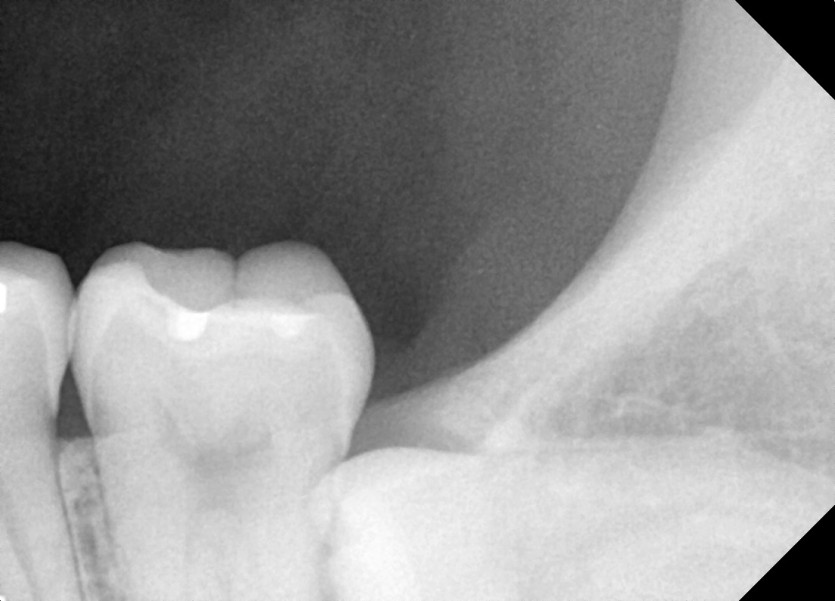

#38 사랑니 발치

구강 외과 전문의가 당일 발치했습니다.